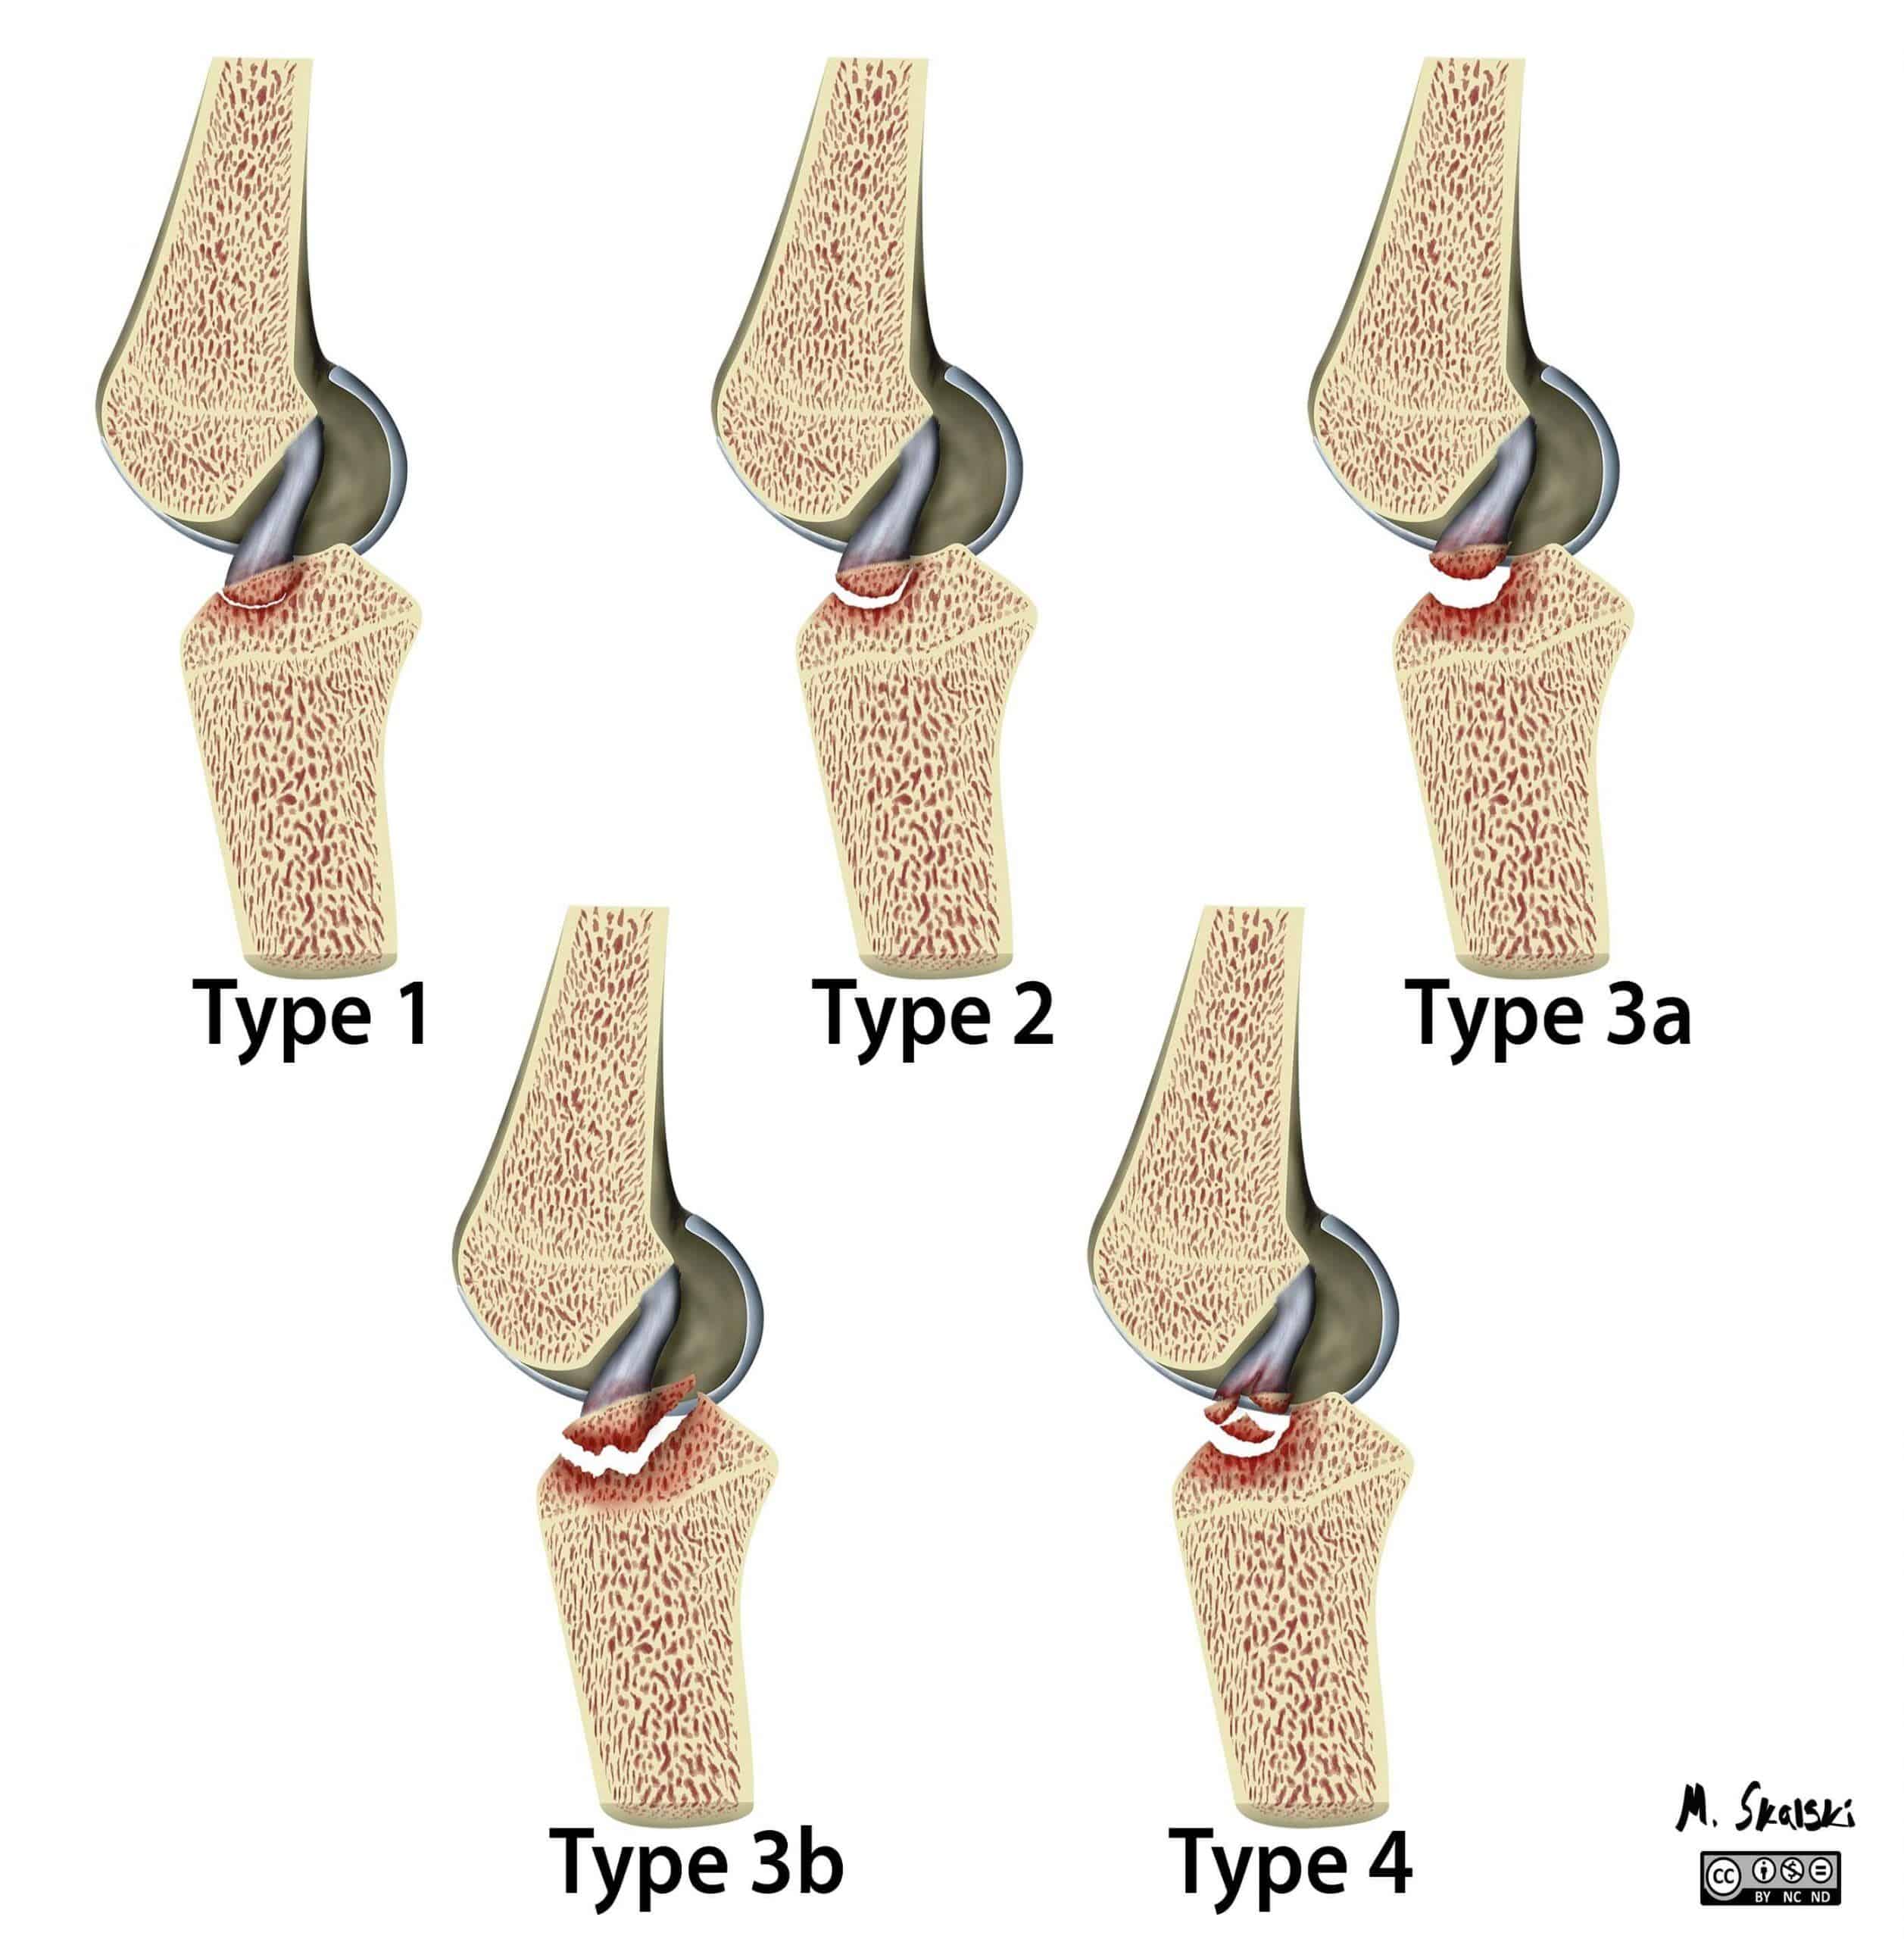

– Khớp gối bao gồm phần dưới của xương đùi và phần trên của xương chày (được gọi là mâm chày), đầu trên xương mác và xương bánh chè. Đầu xương được bọc bởi lớp sụn khớp. Một lớp sụn đệm vào giữa chúng gọi là sụn chêm trong (hình chữ C) và một lớp sụn bên ngoài gọi là sụn chêm ngoài (hình chữ O).

– Hai đầu xương được giữ lại với nhau bằng các dây chằng, ở hai bên là dây chằng trong và dây chằng ngoài, ở trung tâm khớp là dây chằng chéo trước và dây chằng chéo sau. Xương bánh chè là một xương vừng, nó nằm ở dưới gân cơ tứ đầu đùi và có vai trò bảo vệ gân tứ đầu cũng như tăng cánh tay đòn của gân này.